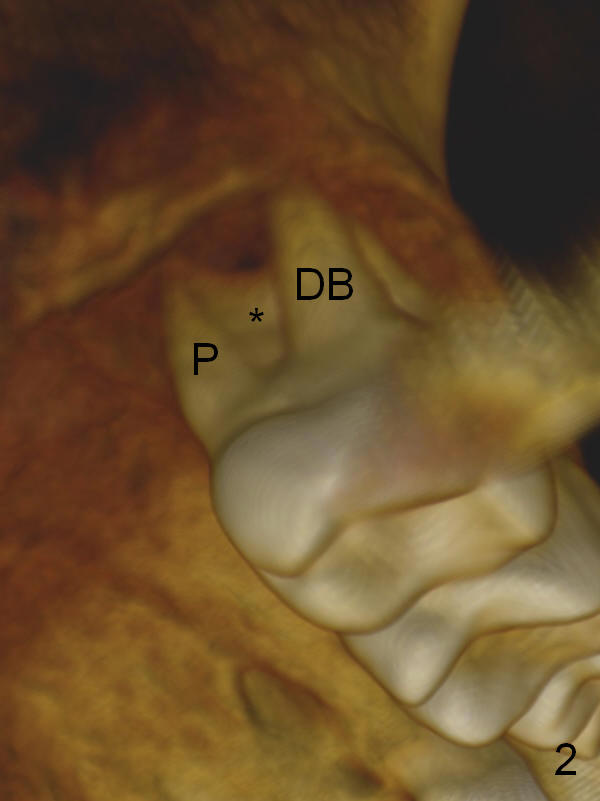

The socket is wider buccopalatally (Fig.2 (3-D disto-occlusal view),3 (coronal section)) than mesiodistally (Fig.1,4 (sagittal section),5 (axial section)). Unless more bone loss has occurred in the last year, a 6x10 mm UF implant is to be placed in the middle of the socket (Fig.6, (soaked with 2% Xylocaine/1:50,000 Epinephrine gauze)) with bone graft to be placed in the buccal and palatal gaps (red circles). Bone density in the middle of the socket is 550-700 Hounsfield units. Use RT2 or 2 mm pilot drill to start osteotomy ~ 3 mm. The largest osteotome is RT4, or largest reamer 4 mm, followed by 4.5x17 mm tap at 14 mm, until 6x17 mm one. Make sure that the sinus floor is penetrated.